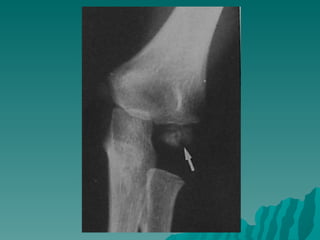

RADYOLOJİ:

 Crescent  sign,

en iyi frog leg

lateral

pozisyonda

görülür.

 Perthesin en

erken X-Ray

bulgusudur.

 (Femur

başında

radyolusen

çizgi- yarık)

 Crescent sign, en iyi frog leg lateral pozisyonda görülür.  Perthesin en erken X-Ray bulgusudur.  (Femur başında radyolusen çizgi- yarık)